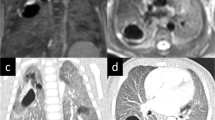

Bronchopulmonary sequestration in a 3-month-old boy. a Coronal proton density MR image shows consolidation in the left lower lobe (**) and prominent vessels with flow voids. b Left anterior oblique volume rendered angiographic view shows the lung lesion (**), its systemic arterial supply (arrowhead) from the descending aorta and venous drainage (arrow) to the left lower pulmonary vein. c, d Coronal image at peak pulmonary enhancement (c) shows a perfusion defect (**) and parametric map (enhancement integral) (d) shows increased perfusion (**) compared to normal lung (* in c and d)

Most bronchopulmonary sequestrations (6/7, 85.7%) presented as consolidation (Fig. 5). Highly intense linear or branching structures were seen centrally in isolated overinflation (7/17, 41.2%) (Fig. 4), in bronchopulmonary sequestration (6/7, 85.7%) and in hybrid lesions (2/3, 66.7%).

The four lung areas with systemic perfusion in scimitar syndrome were hardly detectable on morphological sequences but were clearly evident as perfusion defects on images at peak lung enhancement.

All bronchopulmonary lesions presented as perfusion defect at peak lung enhancement (Figs. 3, 4 and 5). All isolated overinflation showed decreased peak enhancement, with a pulmonary arterial peak in 5/17 (29.4%) lesions and a delayed peak in 12/17 (70.6%). Sequestrations showed delayed and increased (4/7, 57.1%), similar (1/7, 14.3%) or decreased (2/7, 28.6%) peak enhancement compared to normal lung parenchyma. Lung lesions with detectable systemic arteries showed significantly higher enhancement ratios than those without a detectable systemic artery (mean±SD: 0.97±0.62 vs. 0.40±0.23, P=0.009, independent samples t-test) but no significant difference in the delay of peak enhancement (mean±SD: 2.9±1.2 s vs. 2.1±2.0 s, P=0.237, independent samples t-test). Median and interquartile range for the delay of peak enhancement was 2.8 s (0.5 to 4.0 s) for all non-cystic pulmonary lesions. Perfusion parameters for the different lung lesions are detailed in Table 4.

The dynamic contrast-enhanced series helped detect bronchopulmonary lung lesions as they all presented as a perfusion defect during peak pulmonary enhancement. In addition, the dynamic series allowed the differentiation between atelectasis with increased signal intensity and consolidation as part of the lung lesion with perfusion defect at peak pulmonary enhancement. Systemic arterial supply and abnormal pulmonary venous drainage of the lung lesions could be detected on angiographic images from the dynamic contrast-enhanced series, while the evaluation of parenchymal perfusion allowed the further description of the vascular supply of pulmonary abnormalities. Lung areas of overinflation, bronchopulmonary sequestrations, hybrid lesions and normal lung parts supplied by systemic arteries showed delayed peak enhancement of about 2 to 4 s, which indicates predominantly systemic arterial supply of these lesions due to either absent pulmonary arteries or decreased pulmonary arterial perfusion as a sequelae of hypoventilation and decreased oxygen saturation. While contrast-enhanced CT may delineate small vessels comparable to MRI, the perfusion information obtained with a dynamic MRI series is novel in the investigation of congenital lung lesions.